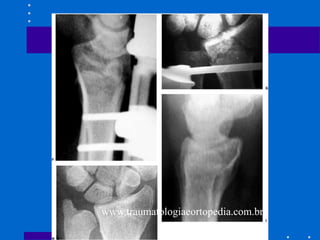

Fixação interna - Placa volar

• Devido às complicações antes citadas,

muitos autores têm indicado fixação das

fraturas dorsalmente deslocadas através de

abordagem palmar - não dá apoio contra

dorsal deslocamento

• cuidar último parafuso para não penetrar

articulação

• Não pode haver cominuição dorsal

• Abordagens

# entre flexor radial do carpo e artéria radial

– melhor exposição para coluna

radial(estilóide)

#entre flexores e feixe ulnar – acessa coluna

intemediária(fossa lunar)

• Fig 26-25

• Fig 26-26

• Fig 26-27

Fratura Articular Palmar

Cisalhamento

• Redução anatômica articular e compressão

através da fratura

• Placa de apoio palmar é ideal

• Cuidar: placa deve apoiar fossa lunar e se

fratura dorso radial a placa submoldada

pode deslocar dorsalmente o fragmento

distal

• Fig 26-29

A,B Tração não reduziu córtex palmar C,D Placa

volar com cominuição estilóide radial residual E,F

placa de coluna radial utilizada( pode ser Fio K)